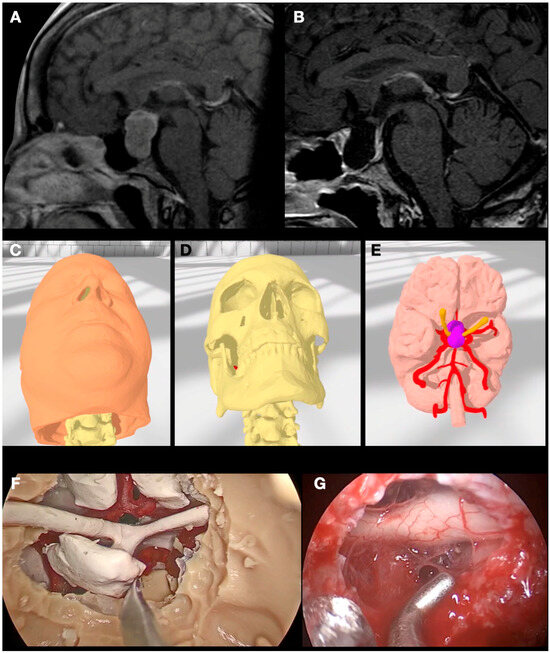

3.4. Case 4: Foramen Magnum Meningioma